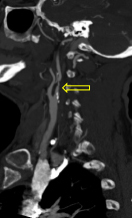

A CT angiogram is ordered for the patient. Results are shown in Figure 3.

Figure 3. The patient’s CT angiography scan showing (A) intracranial axial view and (B) right carotid sagittal view.

The patient’s CT angiography scan shows she suffered abrupt cessation of blood flow due to occlusion of the right internal carotid artery terminus and right middle cerebral artery but maintained some distal cerebral collateral flow (Figure 4A). The likely etiology of the patient’s occlusion is symptomatic carotid atheroemboli from severely stenotic proximal right cervical internal carotid artery (Figure 4B), and recanalization should be considered for secondary stroke prevention moving forward. (Further discussion of this is beyond the scope of this case.)

A.

Figure 4. Patient’s CT angiography scan (from Figure 3). Figure 4A shows abrupt cessation of blood flow caused by the occlusion of the right internal carotid artery terminus and right middle cerebral artery (solid yellow arrow) while maintaining some distal cerebral collateral flow (white arrows). On Figure 4B, the open yellow arrow points to the symptomatic carotid atheroemboli from severely stenotic proximal right cervical internal carotid artery.